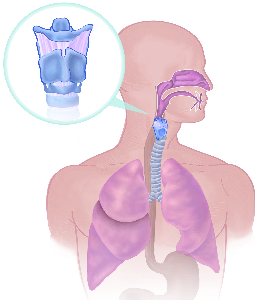

Detailreiche Fotografien aus der medizinischen Praxis ergänzen die Texte; moderne, genaue,

wissenschaftliche Zeichnungen geben Einblick in die Anatomie und die Funktion der Lunge und

anderer Organe.